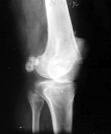

Osteocondromatosis

Osteocondromatosis. Es una enfermedad rara, autosómica dominante en un error genético de los resultados de crecimiento de los huesos en la formación de los osteocondromas múltiples.

Aparece similar a osteocondromas solitarios, aunque con frecuencia las lesiones múltiples son más desorganizadas en la estructura y tienden a tener tapas abollonadas.